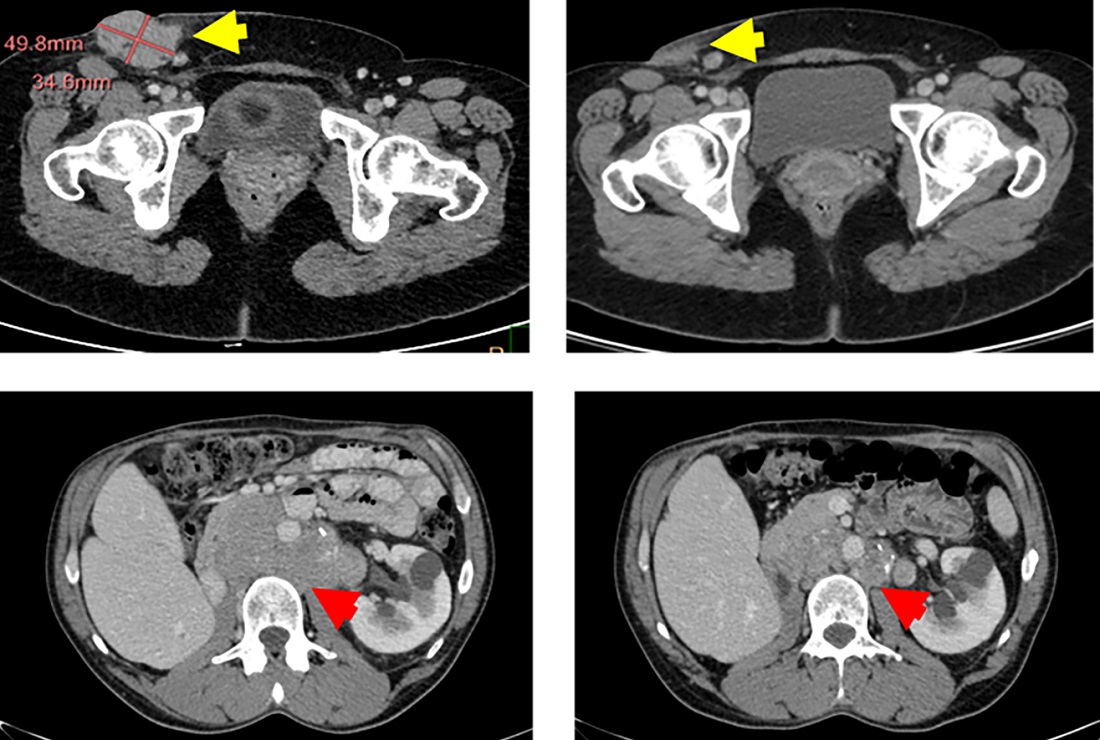

An exploratory randomized controlled clinical trial of #renalcell carcinoma identifies molecular patterns distinguishing responders to immune #checkpointblockade alone or combined with angiogenesis inhibitor versus angiogenesis inhibitor alone: https://t.co/nhahWTufeU